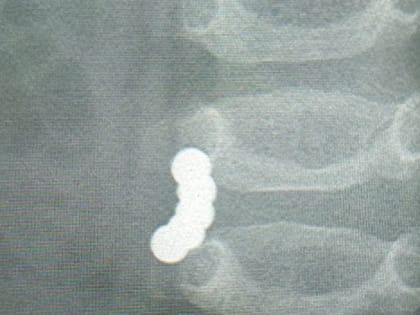

Томские врачи извлекли из кишечника годовалого ребенка пять "магнитов-убийц"

Томские врачи извлекли из кишечника годовалого ребенка пять "магнитов-убийц".